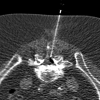

Lumbar epidural injections are typically performed blindly or with fluoroscopic guidance. CT fluoroscopy (CTF) can be used to guide needle placement precisely and rapidly, allowing visualization of the optimal needle path and identifying potential problems such as severe stenosis and synovial cysts before needle insertion. Operator and patient radiation dose is minimal when using the intermittent CTF technique and low mAs. By using this technique, just more than 2000 epidural steroid injections have been performed with no major complications. CTF is a useful guidance tool when performing lumbar epidural injections.